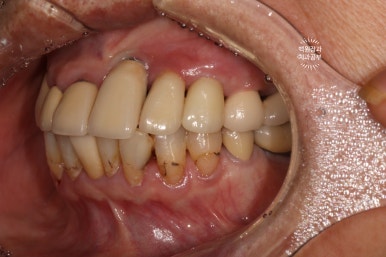

처음 오셨을 때 정면 사진입니다.

잘 보시면, 아까 보였던 치과용 파노라마 사진대로 뿌리만 남은 두 개의 치아를 찾아보실 수 있으실거에요. ㅎㅎ

아까 말씀드렸듯, 왼쪽 위 송곳니와 오른쪽 아래 작은어금니에 뿌리만 있는 잔존치근이 관찰됩니다.

개인적으로 이를 뽑으면서 동시에 심어내는 발치 즉시 임플란트에 보수적인 의사입니다만,

이렇게 비록 치아가 썩어서 부러졌을지언정 만성치주염없이 건강한 잇몸뼈를 가지신 분은 충분히 고려해볼만 하죠!!

좌측은 위턱 사진, 오른쪽은 아래턱 구강내 사진입니다.

아주 어렵지 않게 두 치아가 부러져 있다는 것을 확인할 수 있죠.